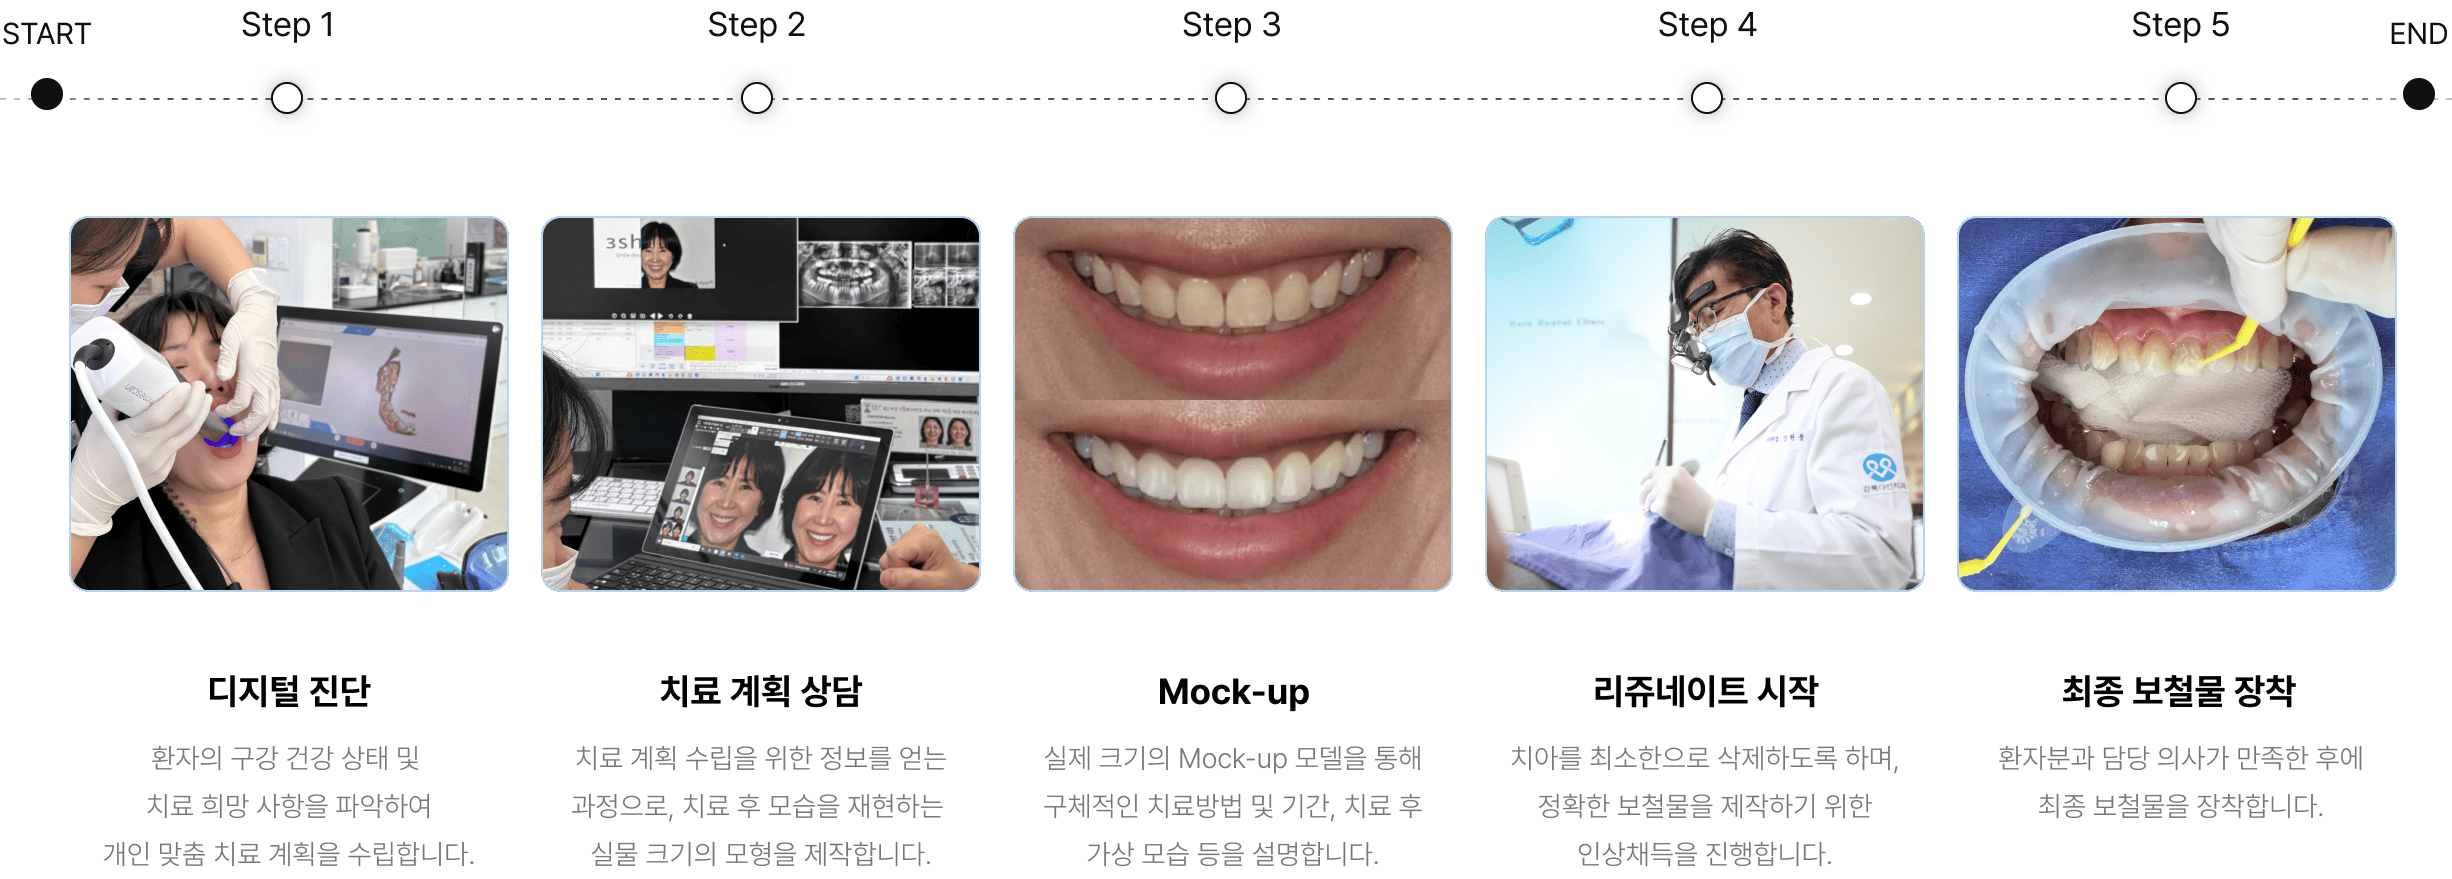

디지털 디자인 시뮬레이션과 Mock-up으로 환자 스스로 디자인과 색 선택이 가능하며,

다인치과의 리쥬네이트는 0.01mm의 최소한의 치아 삭제만으로 시술이 가능하며,

경우에 따라 전혀 삭제하지 않는 무삭제 라미네이트도 가능합니다.